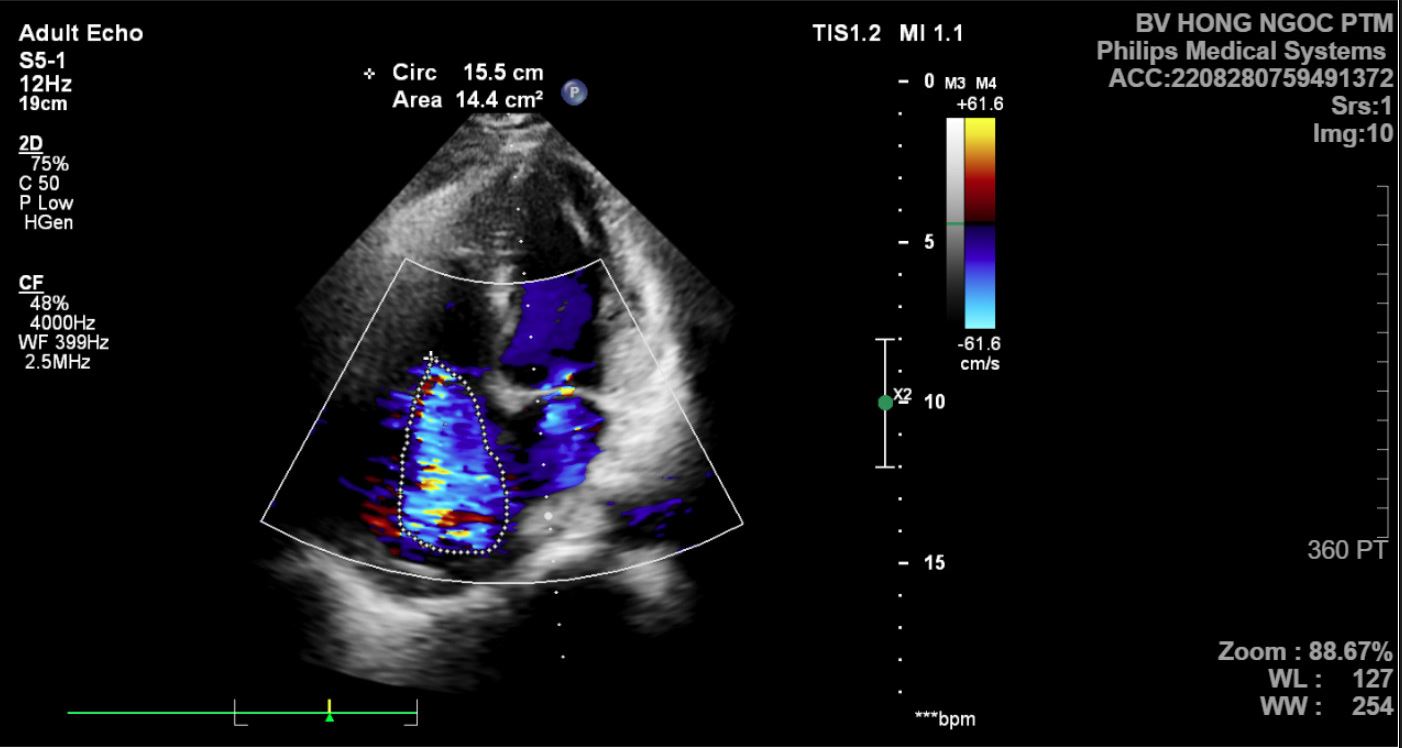

Một trường hợp khác là trường hợp bệnh nhân N.Q.G, 63 tuổi, ở Cao Bằng đến khám với lý do nhịp tim chậm và mệt. Kết quả khám phát hiện bệnh nhân bị block nhĩ thất cấp 3, hở van hai lá vừa, hở van 3 lá nhiều, thông liên nhĩ lỗ thứ 2, tràn dịch màng phổi 2 bên. Bệnh nhân đã được cấp cứu cấy máy tạo nhịp tim thoát khỏi tình trạng nguy hiểm.

width= Diện tích hở van 3 lá (phần được khoanh) lớn tới 14,4cm2